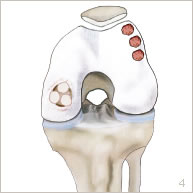

Une lésion cartilagineuse peut survenir lors d’un choc, à la suite de petits traumatismes répétitifs, ou à la suite d’une imperfection de la croissance. Le cartilage ainsi abîmé se décolle seul de son emplacement naturel ou accompagné d’une petite partie osseuse sous-jacente (figures 2 et 5). Il peut se détacher partiellement sous forme d’un clapet, ou bien complètement constituant ainsi un fragment libre. La zone de défect cartilagineux peut être plus ou moins étendue et plus ou moins profonde. La lésion cartilagineuse peut occasionner des douleurs, des blocages, des gonflements voire des sensations d’instabilité. Des lésions ligamentaires ou méniscales peuvent être associées.

Une ou plusieurs carottes ostéo-cartilagineuses sont prélevées à partir d’une zone peu sollicitée en périphérie du fémur à l’aide d’un instrument spécifique (figure 3). L’os du défect est préparé pour recevoir la greffe. Enfin, les carottes ostéo-cartilagineuses sont impactées côte à côte comme une vraie mosaïque pour reformer une surface de glissement homogène (figures 4, 6 et 7).